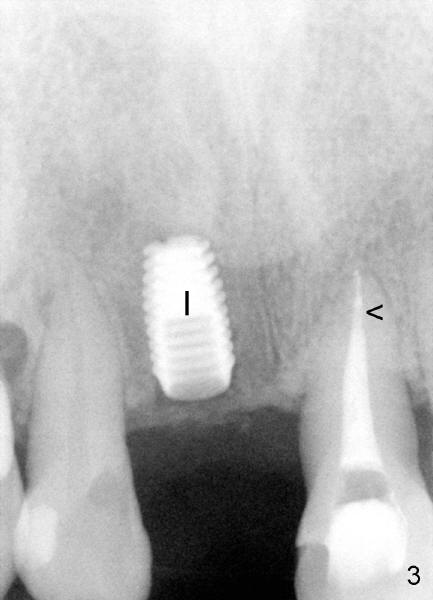

Fig.2 pre-op: #8 endo-perio disease, nonsalvageable; #9 RCT short fill (black arrowhead) with periapical radiolucency (red arrowhead). Fig.3: 15 months after RCT retreat (arrowhead), the periapical radiolucency of #9 isappears; 12 months after extraction of #8, Bicon 4.5x8 mm implant placed (I). Return to original article